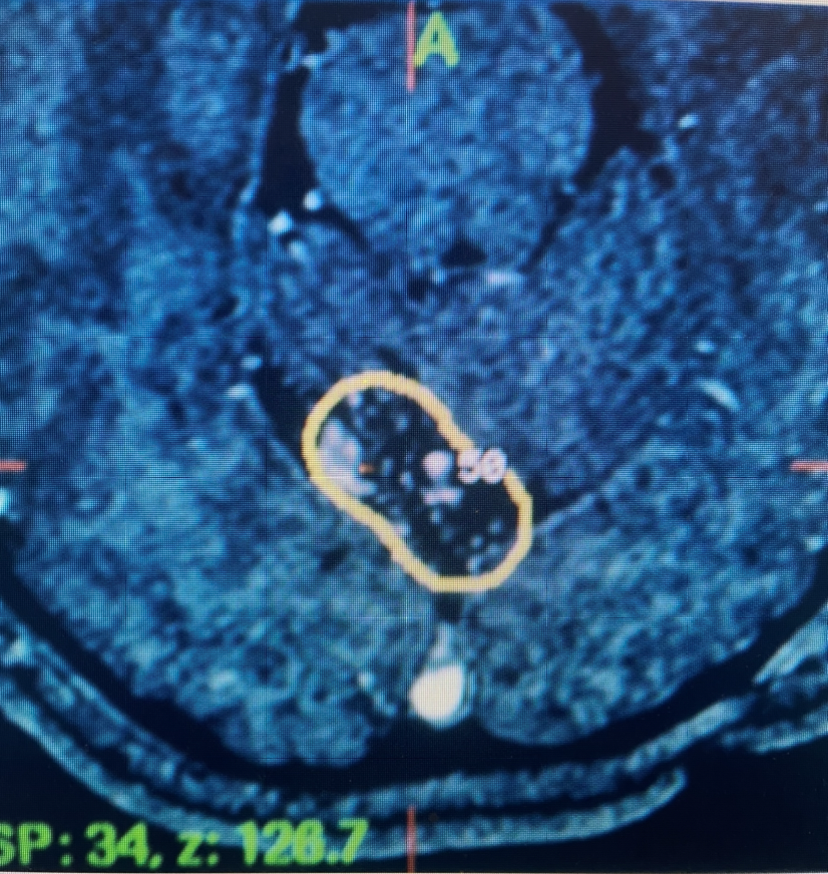

Subsequent to this, she underwent Gamma Knife treatment of the cerebellar AVM (figure 1) with Dr. Michael Brisman. She had no subsequent problems. Subsequent imaging showed that the AVM was starting to thrombose. She was then lost to follow up for many years.

Figure 1. Axial MRI with contrast at the time of gamma knife treatment showing the tightly conformal 50% Isodose line contoured around the AVM of the posterior superior cerebellar vermis.